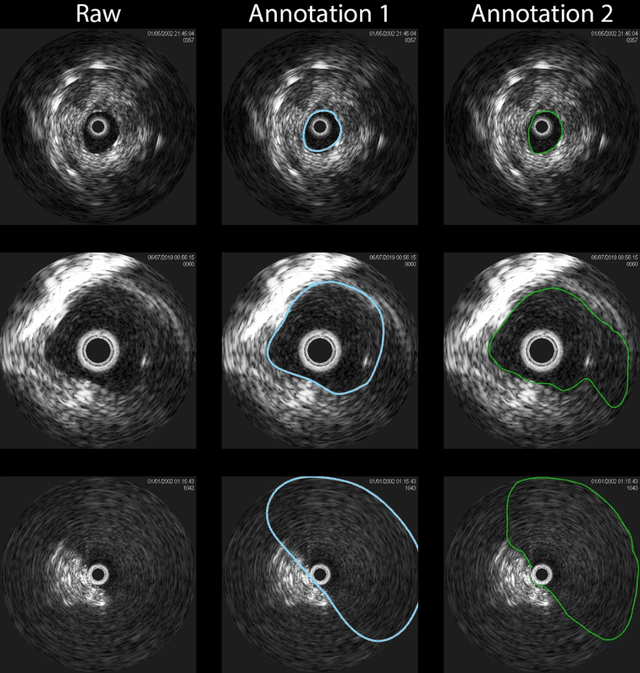

Development of deep learning systems for biomedical segmentation often requires access to expert-driven, manually annotated datasets. If more than a single expert is involved in the annotation of the same images, then the inter-expert agreement is not necessarily perfect, and no single expert annotation can precisely capture the so-called ground truth of the regions of interest on all images. Also, it is not trivial to generate a reference estimate using annotations from multiple experts. Here we present a deep neural network, defined as U-Net-and-a-half, which can simultaneously learn from annotations performed by multiple experts on the same set of images. U-Net-and-a-half contains a convolutional encoder to generate features from the input images, multiple decoders that allow simultaneous learning from image masks obtained from annotations that were independently generated by multiple experts, and a shared low-dimensional feature space. To demonstrate the applicability of our framework, we used two distinct datasets from digital pathology and radiology, respectively. Specifically, we trained two separate models using pathologist-driven annotations of glomeruli on whole slide images of human kidney biopsies (10 patients), and radiologist-driven annotations of lumen cross-sections of human arteriovenous fistulae obtained from intravascular ultrasound images (10 patients), respectively. The models based on U-Net-and-a-half exceeded the performance of the traditional U-Net models trained on single expert annotations alone, thus expanding the scope of multitask learning in the context of biomedical image segmentation.